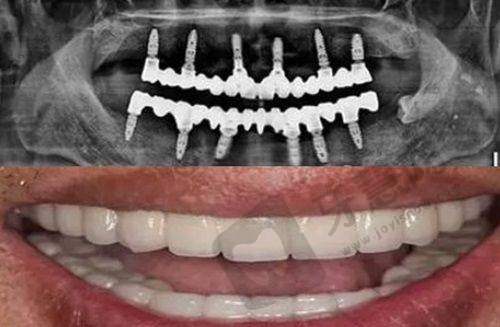

广州博海口腔医院的诊疗服务那是相当全方面。首先,它开展的口腔诊疗项目特别齐全,不管是种植牙、牙齿矫正,还是美学修复、牙周炎治疗,亦或是补牙、拔牙、全瓷牙修复、儿牙治疗、洗牙等等,都能在这里得到专精的诊疗,因此吸引了不少忠实粉丝。就拿种植牙来说,对于那些牙齿缺失的患者,医院的医生能够根据患者的口腔状况,选择合适的种植体,帮助患者修复咀嚼功能,重新拥有健康的牙齿。牙齿矫正也是医院的强项之一,医生会根据患者牙齿的具体情况,制定个性化的矫正方案,让患者在矫正过程中更加舒适,矫正成效也更加理想。

为了给大众提供更加舒适、优质的口腔就诊和治疗体验,广州博海口腔医院搭建了数字化的就诊流程和治疗体系。通过三维口扫设备,能够快速获取详细的口腔和牙齿信息,并直接传给医生。以前患者看牙,可能要做各种检查,拿着牙片到处跑,现在有了数字化体系,这些麻烦都没有了,节省了患者大量的时间和精力。而且,数字化诊疗体系还可以模拟口腔治疗的过程,在种植牙、牙齿矫正等方面广泛应用,大大减少了手术风险,缩短了治疗时间。就像在做种植牙手术前,医生可以通过模拟治疗过程,提前规划好种植体的位置和角度,让手术更加精细。

广州博海口腔医院医生的技术在当地是有口皆碑的。他们凭借丰富的临床经验和扎实的学术背景,能够解决各种口腔问题。在种植牙方面,医生能够熟练掌握种植技术,确保种植体的稳定性和成功几率;在牙齿矫正方面,能够根据不同患者的牙齿情况,选择合适的矫正方法,让患者的牙齿变得更加整齐美观。特别多患者都是冲着医生的技术来的,而且经过治疗后,都对医生的技术赞不绝口。